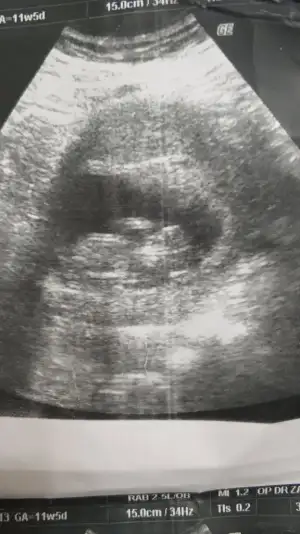

Malesef bir tek bu var 11+5 olarak başka yok11 12 13 haftalar nub için uygun şimdilik sanki erkek gibi gibi dediğimiz usgleri paylaşırmısınız

Net değil usgMalesef bir tek bu var 11+5 olarak başka yok![]()